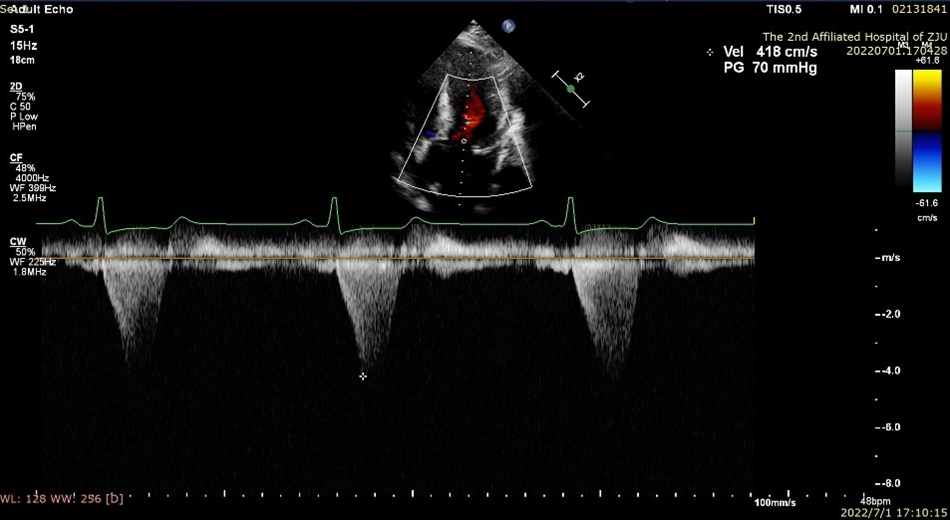

2022年7月1日在浙江大学医学院附属第二医院导管室,应用Liwen RF射频消融系统经心尖到达肥厚室间隔进行射频消融,术后即刻超声显示靶区消融充分,术后即可左室流出道压差显著降低。

病例2

患者是一位58岁的女性。超声提示患者室间隔最大厚度为26.3mm,静息状态左室流出道压差为118mmHg,负荷状态下为233mmHg。

术后左室流出道压差